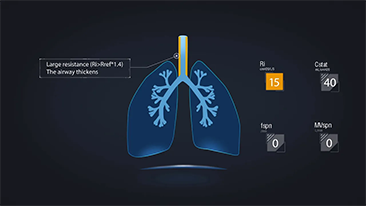

Progettati a partire da un'analisi approfondita delle esigenze cliniche dei pazienti e degli operatori sanitari, i ventilatori Mindray rispondono ai requisiti delle terapie sequenziali che comprendono ossigenoterapia, ventilazione non invasiva e ventilazione invasiva offrendo prestazioni stabili, funzioni versatili e semplicitĂ di utilizzo. Le modalitĂ di ventilazione e gli strumenti di supporto al processo decisionale sono sviluppati sulla base delle esigenze cliniche e delle linee guida professionali per aiutare il personale medico a prendere decisioni cliniche in tutta calma per tutti i pazienti e i livelli di gravitĂ .

Integrando ossigenoterapia ad alti flussi, ventilazione non invasiva e ventilazione invasiva in un unico dispositivo, i ventilatori 3 in 1 della serie SV offrono prestazioni stabili, funzioni versatili e semplicitĂ di utilizzo. Le eccezionali funzionalitĂ per la protezione polmonare e i numerosi strumenti di supporto al processo decisionale sono stati progettati per ridurre il rischio di trasmissione crociata delle infezioni e per semplificare la routine quotidiana degli operatori sanitari.